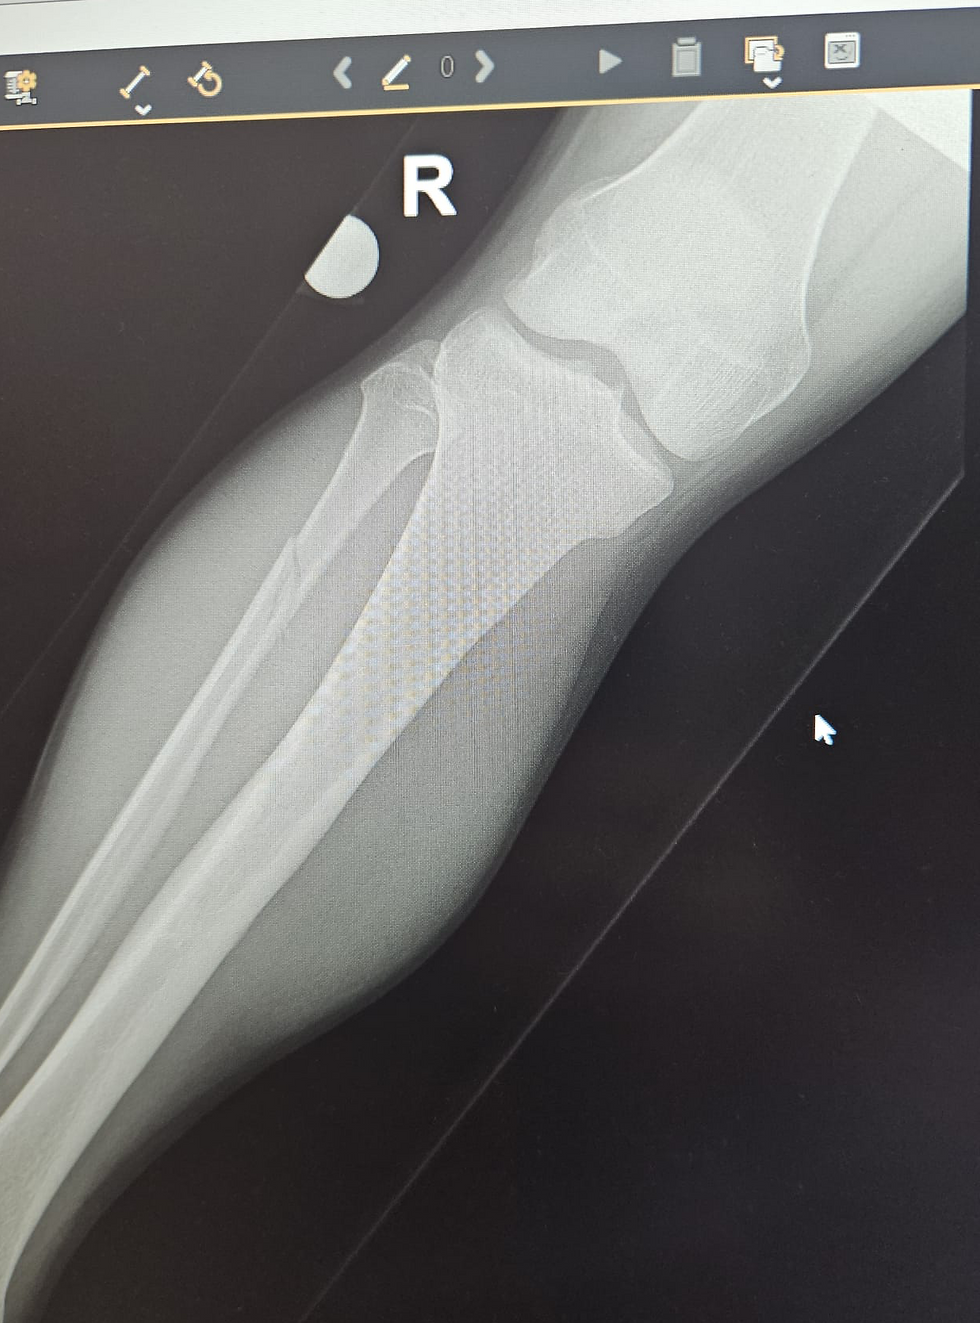

Das Wadenbein ist gebrochen, das vordere Syndesmoseband gerissen und das hintere Syndesmoseband gezerrt, das Innenband angerissen, 2-3 kleinere Bänder im Fuss sind ebenfalls gerissen, abgerundet wird die Serie von Verletzungen von Absplitterungen am Schienbein, welche aber nicht operiert werden müssen.

Die Stabilisierung des Schien- und Wadenbeins mit einem Kunstband, ausgeführt von Dr. med. Andreas Klakow, ist erfolgreich verlaufen. Nun folgt eine 6-wöchige Ruhephase ohne Belastung, bevor zum langwierigen Aufbau geschritten werden kann.